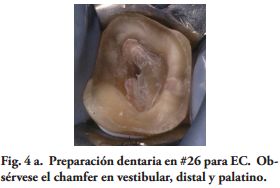

Por su parte, varios estudios clínicos, concluyeron que el remanente coronario es el factor más importante en el éxito clínico del DET (18-21). Por lo tanto, un criterio conservador es esencial en la preparación dentaria para un EC. Toda la superficie oclusal debe ser cubierta por la restauración, teniendo en cuenta la función oclusal del paciente. Los onlays transmiten fundamentalmente, fuerzas compresivas en la interfase adhesiva restauración - diente, mejorando el comportamiento biomecánico (22-24). Para este procedimiento restaurador fue sugerido un espesor oclusal de 3 mm. (25) y aumentando el mismo la resistencia a la fractura sería más alta (26). Además. si las paredes vestibular y/o palatina o lingual, tienen un espesor mayor de 2.0 mm., un chamfer de 1.2 mm. en oclusal de estas paredes, podrían tener un efecto zuncho o abrazadera, aumentando la resistencia a la fractura de los dientes y la retención de la restauración (Figs. 3a, 4a).

Las paredes internas de la corona dentaria y de la cámara pulpar, deben tener una divergencia hacia oclusal mayor de 60 y si presentan depresiones o zonas retentivas, deben rellenarse con cemento de ionómero de vidrio. El operador, dispensa una fina capa del mismo cemento en el piso cameral. En este estudio cuatro preparaciones tenían 3 paredes coronarias (Figs. 1b, 2a), cuatro 2 paredes (Fig. 3a) y en 2, las restauraciones abarcaban 4 paredes coronarias.

Los autores de este trabajo, consideran que extender la preparación a la cara vestibular está condicionada por requerimientos estéticos o reducidas dimensiones de la misma. En esta situación clínica (Fig. 4a), una reducción axial de 1.2 mm. de la pared vestibular fue suficiente. En vestibular, distal y palatino, el borde cavo de la preparación se definió en forma de chamfer. Estos criterios no concuerdan con la reducción total de la corona dentaria, propuesta por Fages y Benassar (9).